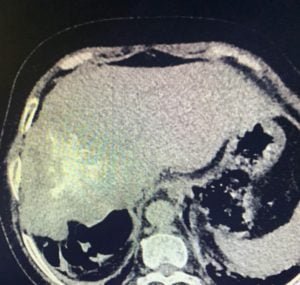

Contrast enhanced CT scan abdomen showed a non enhancing infiltrating hepatic solid mass that contains multiple cystic-necrotic hypodense areas and hyperattenuating foci of internal calcifications .

Infiltration into hepatic veins and intrahepatic IVC was also noted.

Fig CT scan abdomen showing liver mass